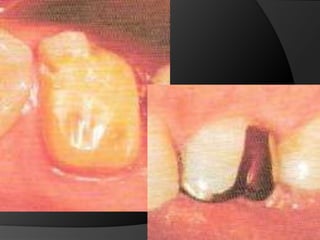

fundamentos de periodoncia en prótesis fijaCuando, por la evolución de lesiones de caries, fracturas, o necesidad de ganancia de retención mecánica en pilares muy cortos, el espacio biológico es violado, existe la necesidad de restablecer sus dimensiones, como una forma de recuperar la salud del periodonto y de facilitar los procedimientos protésicos

fundamentos de periodoncia en prótesis fijaCirugía de Alargamiento CoronalExtrusión OrtodónticaTécnica Combinada